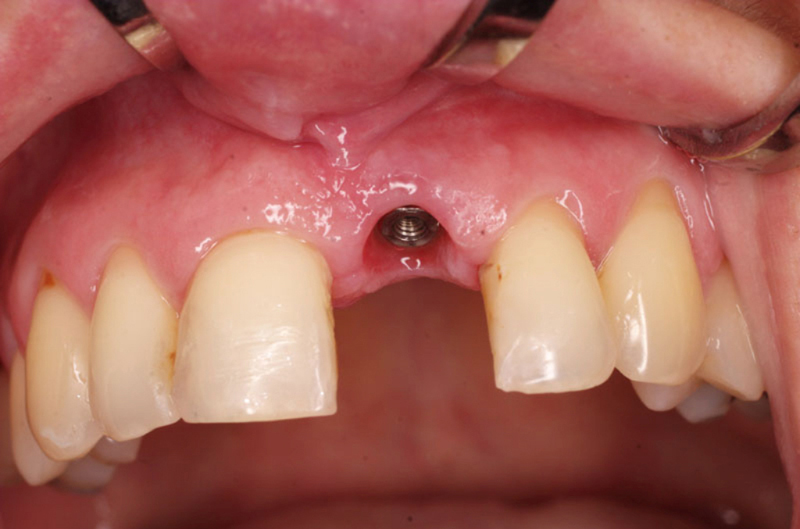

Klasickým příkladem a indikací pro použití implantátu je ztráta jednoho zubu (v tomto případě v předním – frontálním úseku) v jinak zdravém, nepoškozeném chrupu.

Nejčastější příčinou takové ztráty je sportovní nebo dopravní úraz.

Při ošetření pomocí jednotlivých implantátů zůstávají sousední zuby neporušené – intaktní. Při klasickém ošetření pomocí můstků musejí být tyto zuby obroušeny!